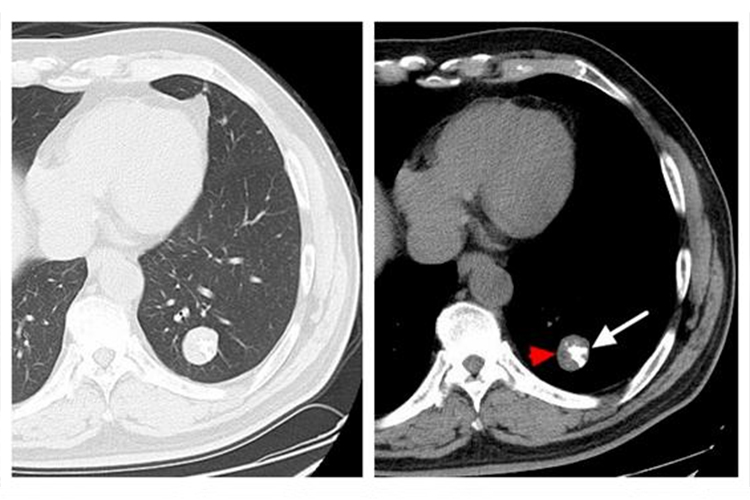

肺部良性肿瘤患者多无不适症状,常在体检时偶然发现,肿瘤形态大多数为圆形、椭圆形、类圆形,密度相对较高。如瘤体巨大,可压迫周围组织,引起咳嗽、气促、胸闷、胸痛等症状。

早期肺部恶性肿瘤往往无症状,随着肿瘤进展,可出现咳嗽、血痰、胸痛、发热、气促等症状。影像学检查主要表现为不规则高密度影,可呈现球形或者分叶状块影。当癌肿继续长大阻塞支气管,可继发肺部感染,痰量增多,伴有脓性痰液。